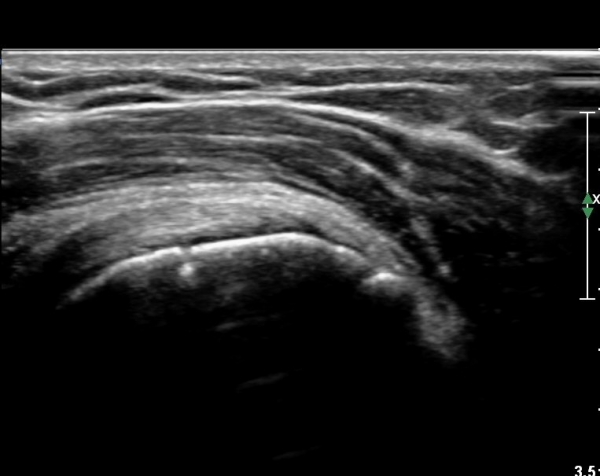

ÃÊÀ½ÆÄ °Ë»ç

´ë°áÀý°ú °ßºÀÇϺο¡ ¹æ»ç¼± Åõ°ú¼º °¨¼Ò(sclerosis)°¡ °üÂûµÈ´Ù(÷ºÎÆÄÀÏ).